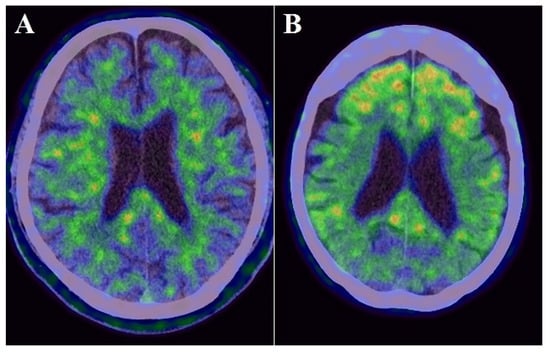

Static PiB-PET and FDG-PET studies were conducted in three-dimensional scanning mode using a Siemens Biograph mCT PET scanner (Siemens) as previously described [,]. The reagents were provided by the PET center of our hospital. Participants received an intravenous bolus injection of PiB [mean ± standard deviation (SD) of radioactivity = 523 ± 47 MBq] and subsequent saline flush in the PiB-PET study. Then, PET images were acquired 50–70 min after the injection. To perform FDG-PET, all participants kept close their eyes and relaxed in a dimly lit room for 10 min before the injection. Then, they received a bolus intravenous injection of 3.0 MBq/kg FDG and subsequent saline flush. PET images were acquired 40–60 min after the injection. The radiation in pre-pose and post-dose samples was measured using a radiation detector for the calculation of injected dose in each participant. All imaging data were reconstructed into a 3.0-mm thick slice, on a 256 × 256 matrix, and at 3.0× magnification with an ordered-subset expectation maximization that includes four iterations and 12 subsets. The reconstructed images had a pixel size of 1.06 mm. The PiB-PET and FDG-PET scans were both spatially normalized to the Montreal Neurological Institute reference space through a customized PET template using Statistical Parametric Mapping version 8 (Wellcome Trust Centre for Neuroimaging, https://www.fil.ion.ucl.ac.uk/spm/) (accessed date 7 October 2021). Regions of interest (ROIs), such as the frontal lobe, temporoparietal lobe, posterior cingulate gyrus, and cerebellum, were determined using the MarsBaR (MRC Cognition and Brain Sciences Unit) ROI toolbox for Statistical Parametric Mapping as described previously []. These ROIs were established as areas with amyloid deposition and decreased cortical glucose metabolism in patients with AD [,]. PiB and FDG uptake was assessed by a standardized uptake value ratio (SUVR). The ROI values were averaged across both hemispheres. The globally standardized uptake value ratio of FDG-PET and PiB-PET was represented as a single mean value for all regions combined (Figure 2 and Figure 3). Higher amyloid uptake was determined using a mean cortical SUVR of 1.4 or higher as the cut off [].

Figure 2.

Examples images of an individual with lower PiB uptake ((A): cortical SUVR value = 0.804) and with higher PiB uptake ((B): cortical SUVR value = 2.584).